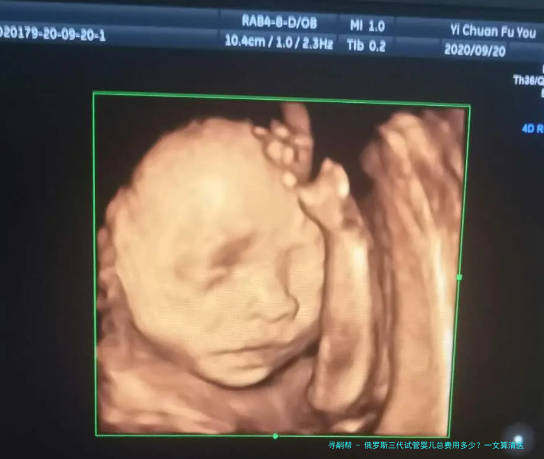

俄罗斯三代试管婴儿总费用多少?一文算清医疗和生活全账单

跟着人类辅助生殖技术的不断发展,越来越多的家庭选择通过试管婴儿技术来实现生育愿望。俄罗斯以其先进的医疗科技和相对偏低的费用,吸引了许多国内患者前往就诊。如此,俄罗斯三代试管婴儿的总花销究竟是多少呢?本文将为您详细梳理俄罗斯三代试管婴儿的医疗费用和赡养费用,让您对整个流程的花费胸有定见。